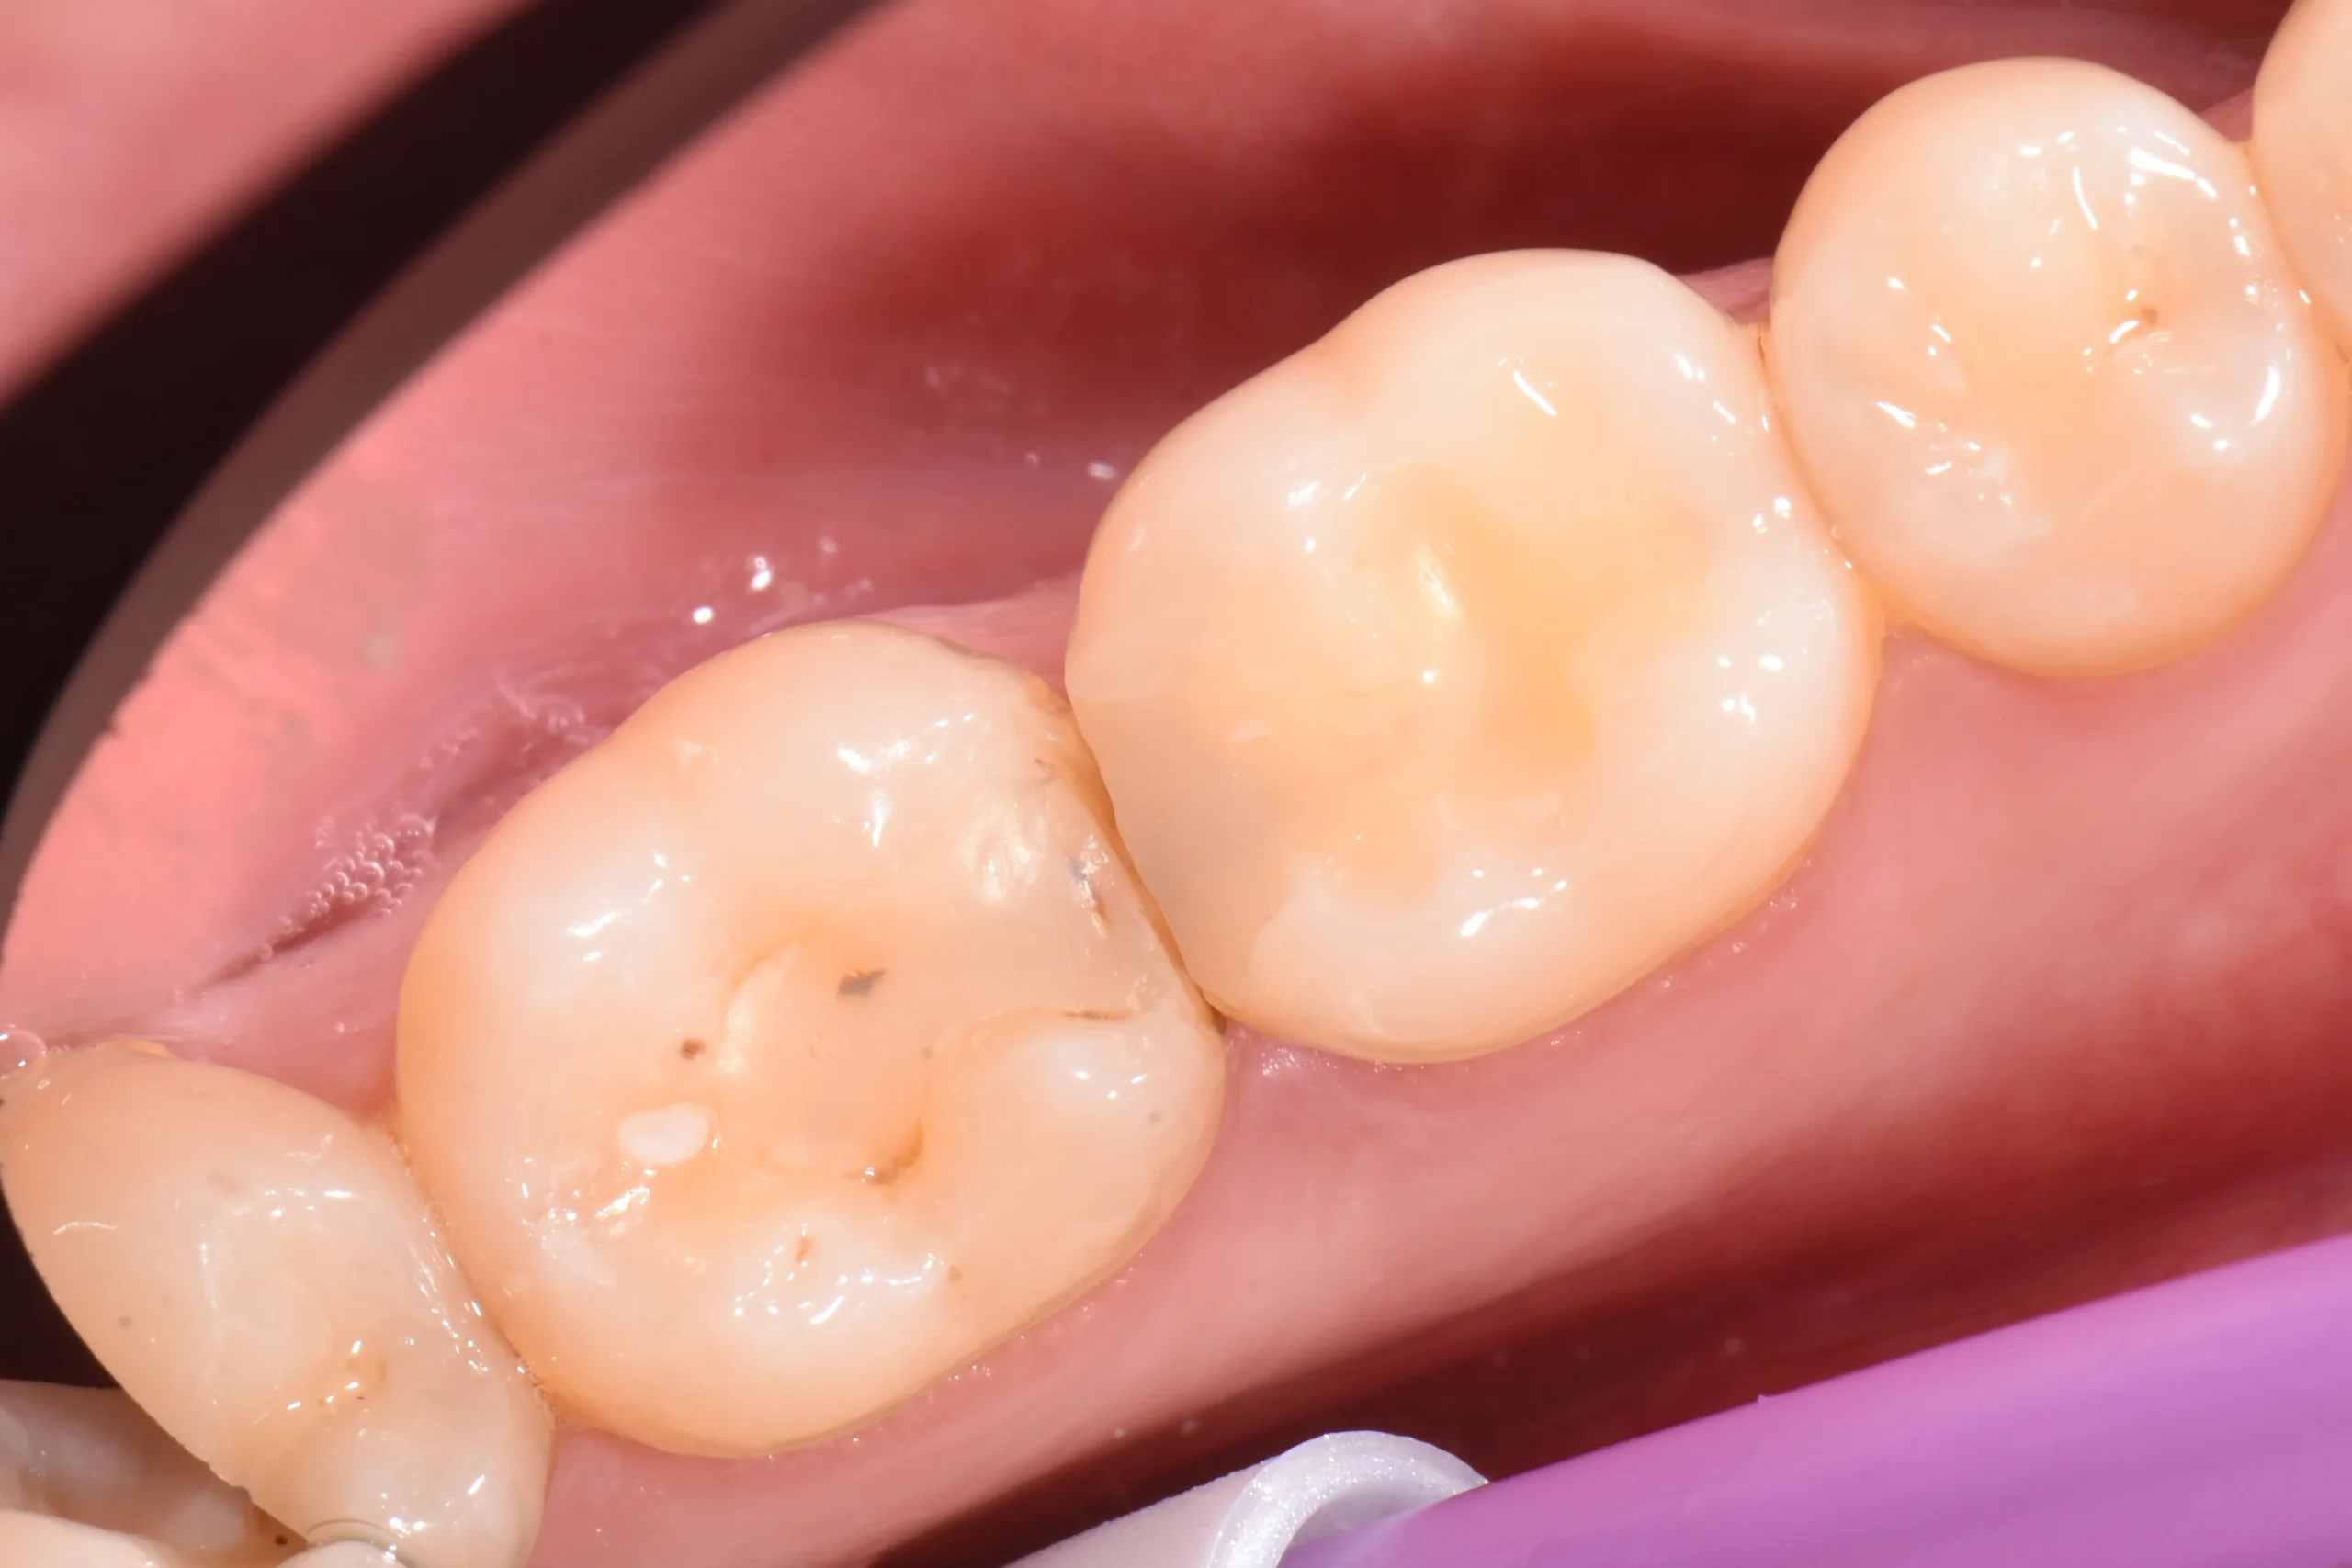

Wir legen besonderen Wert auf eine hochwertige Verarbeitung, denn schlussendlich darf man die handwerkliche Komponente der Zahnmedizin nicht außer acht lassen - was zu erheblichen Qualitätsunterschieden führt, die Sie hier auf einer Makro-Fotoaufnahme sehen können.

Ich gebe mir größte Mühe, dass die Composite Füllung sowohl funktionell wie auch von der Ästhetik her der Vervollständigung Ihres natürlichen Zahnes entspricht.

Ob kleine oder größere Defekte: Mit Composite-Füllungen können wir in den allermeisten Fällen substanzschonend und langlebig versorgen – und das auf hohem ästhetischem Niveau.